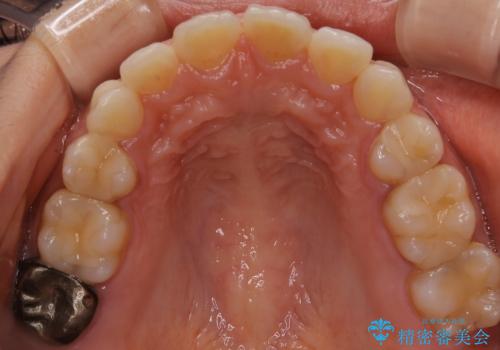

後戻りの程度としては軽度なので、治療期間としては短く終えることが出来ました。

前歯の正中線も改善され大変満足して頂きました。